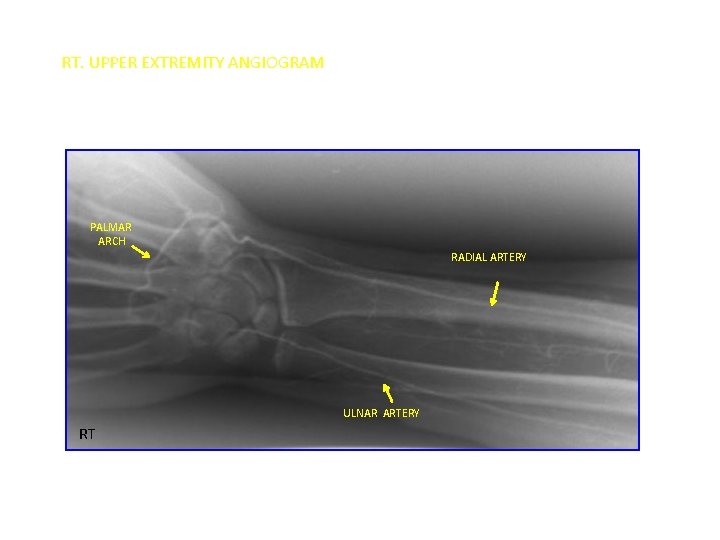

RT. UPPER EXTREMITY ANGIOGRAM PALMAR ARCH RADIAL ARTERY ULNAR ARTERY RT